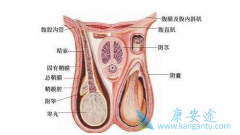

����غ�谩�ķ���������Խ��Խ�ߣ���������������Ϊ������ô�� غ�谩 ��ԭ����ʲô�أ�ԭ����һ��غ����������IJ��˶Բ�غ��ͬ������������������һ�ִ��Ѿ��õ��㷺����ʶ��غ�������ķ����ʼ��ͣ�ԼΪ1/5���ڷ�����غ����������У��Բ�غ�������ķ��� ...

������Ŀǰ��ҽѧ��չ��˵������ غ�谩 �������Ƿdz����ӵģ�����������Σ�յ�����غ����غ�������Գ���ʱغ��δ�ܽ������Ҷ������ڸ�ǻ���γɵġ�����ͨ���������ƣ��䷢�����ļ�����Ϊ�����˵�20�������һֱδ��ȡ�������伸�ʿɴ�50%���ϡ������ʵ ...